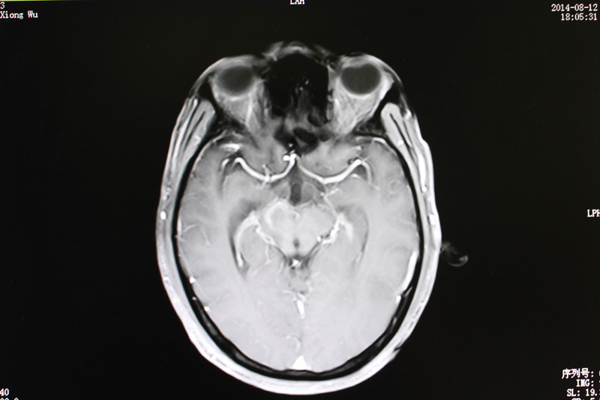

在南宁一家医院进行MRI检查后,黄先生被告知:桥脑、右侧大脑脚及右侧基底节区占位。也就是大脑的重要功能区长出了一个肿瘤。

8月12日,从最新的MRI检查结果上显示,病灶水肿范围较之治疗前明显缩小。

主管医生姜盛强介绍肿瘤治疗效果的标准:“有五个层面,包括恶化(肿瘤继续增大);无变化(肿瘤缩小在25%以下);微效(肿瘤缩小在25%-50%之间);有效(肿瘤缩小在一半以上);显效(肿瘤病灶消失)几个等级。”

“黄先生属于有效,也就是从肿瘤已经明显缩小,肿瘤对脑部神经和组织的压力减小。”

治疗前

治疗后